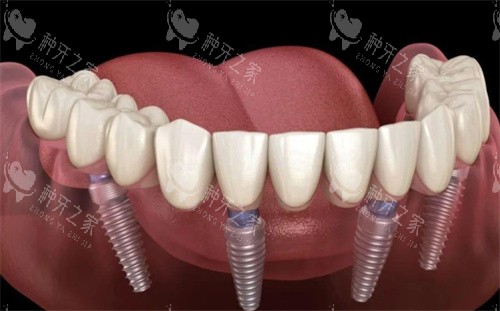

做半口或全口种植牙6年后,使用者普遍收获了咀嚼功能重塑、口腔状态稳定、生活质量提升的正向体验。不同修复技术、不同年龄段的网友,均反...